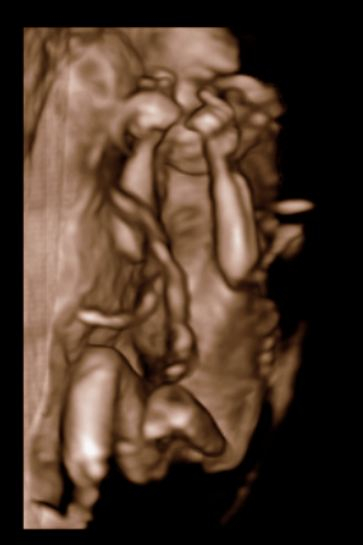

Прекрасные фоточки, мой тоже в прошлом году УЗИ начинал с демонстрации *я мальчик!*